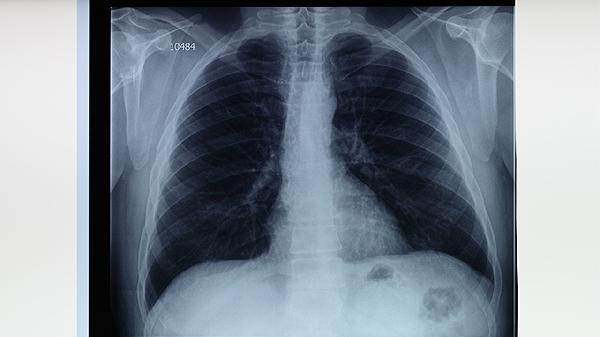

肺结核病人的胸片结果通常表现为肺部阴影、空洞、钙化灶或淋巴结肿大。这些异常影像提示肺部感染结核分枝杆菌,需要结合临床症状和实验室检查确诊。治疗方法包括抗结核药物治疗、手术治疗和支持性疗法。

1、肺结核的胸片特征。肺结核的胸片结果因病情不同呈现多样化。早期表现为局部浸润性阴影,多位于肺上叶或下叶背段。随着病情进展,可能出现空洞,提示肺组织坏死。慢性期可见钙化灶,提示病灶愈合。淋巴结肿大在儿童和青少年中较为常见。胸片结果需与临床症状结合分析,如长期低热、咳嗽、咳痰、盗汗等。

肺结核是一种慢性传染病,及时诊断和规范治疗是关键。通过抗结核药物治疗、手术治疗和支持性疗法的综合应用,大多数患者可以治愈。治疗过程中需要坚持全程、规律用药,避免中断治疗导致耐药性产生。对于高危人群,如密切接触者、免疫抑制患者,建议定期进行结核筛查,早期发现,早期治疗。胸片作为诊断肺结核的重要工具,结合临床症状和实验室检查,能够有效评估病情和指导治疗。